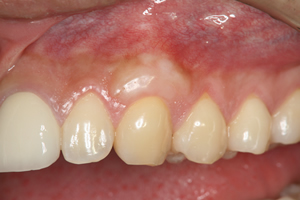

治療前

被せものが装着されている歯の歯肉が下がり、歯根が露出していました。被せものと歯根の色が大きく異なり、不自然な状態でした。